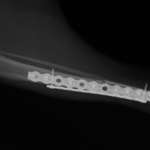

トイプードル 右遠位橈尺骨短斜骨折のALPSによる内固定

当院ではAdvanced Locking plate system(ALPS)と、Locking compression plate system(LCPS)という骨接合法で骨折症例の治療を行っています。

Advanced Locking Plate System

従来型のプレートのように広い面積で骨と接するプレートを用いて固定を行った場合、プレート下の骨はプレートとの接触面において血行が絶たれ壊死し、それがリモデリングされると骨密度が低下する。この骨密度の低下防ぐために、骨折部局所への血行を温存することの重要性が近年改めて認識されるようになってきている。Advaed Locking Plate System (ALPS)は従来型のプレートシステムの欠点を改良し、より使いやすく、より骨への血行を阻害しないようにというコンセプトで作られた。

Advanced Locking Plate System の特徴

- 骨への血行障害は最小限である

- 上下左右にベンディング可能でより3次元的な成形が可能

- すべての部位においてプレート強度は均一である

- ロッキングスクリューと圧着型スクリュー(皮質骨スクリュー)の双方が使用できる

- ダイナミックコンプレッション機能

- 生体親和性の高いチタン製

- トイ犬種から馬まで応用できるサイズ展開がある